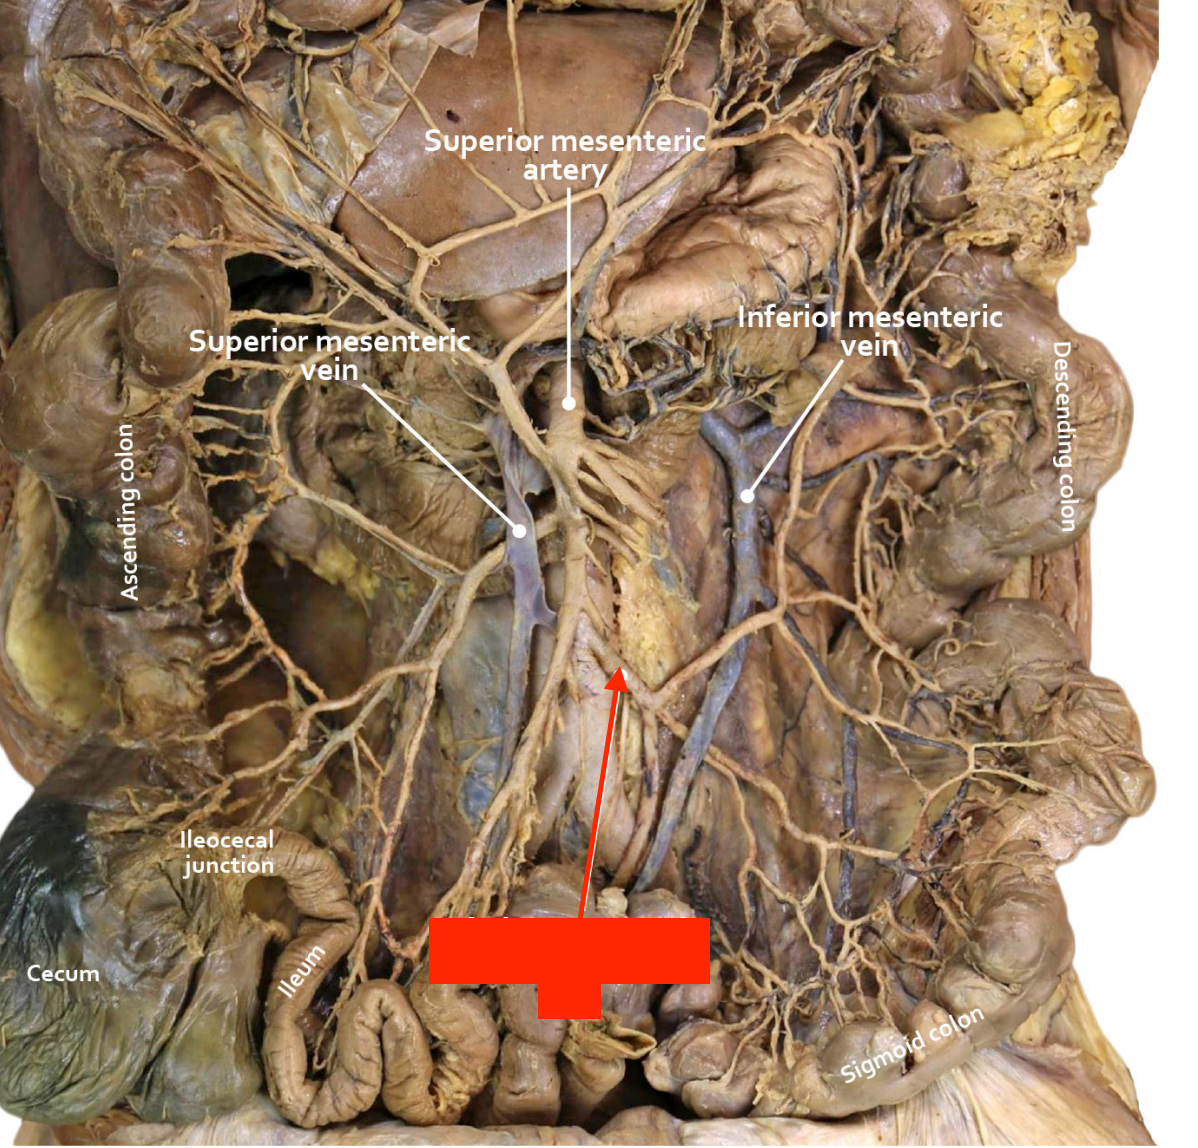

duodenojejunal junction

jejunum

ileum

ileocecal junction

cecum

ascending colon

descending colon

sigmoid colon

superior mesenteric artery

jejunal and ileal arteries

ileocolic artery

right colic artery

middle colic artery

inferior mesenteric artery

left colic artery

sigmoidal arteries

marginal artery